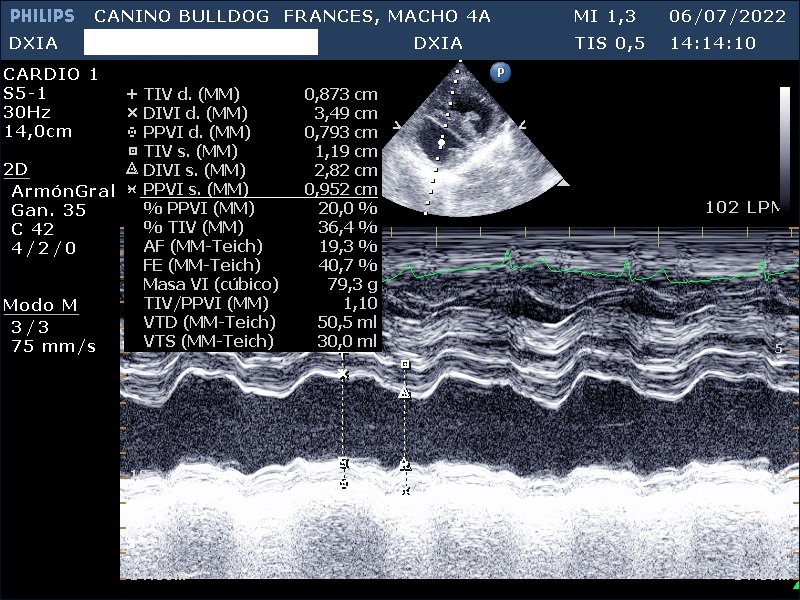

- Válvula mitral: Normoimplantada. No se detectan engrosamientos valvulares, pero las valvas no coaptan correctamente. Estudio Doppler con flujo de regurgitación moderado-severo de Vmáx RM: 504 cm/s y GPmáx RM: 102 mmHg.

Dilatación marcada de cámaras derechas e izquierdas. SSPE VM: 0,952 cm

AF disminuida en 10,7%

Aplanamiento del septo interventricular.